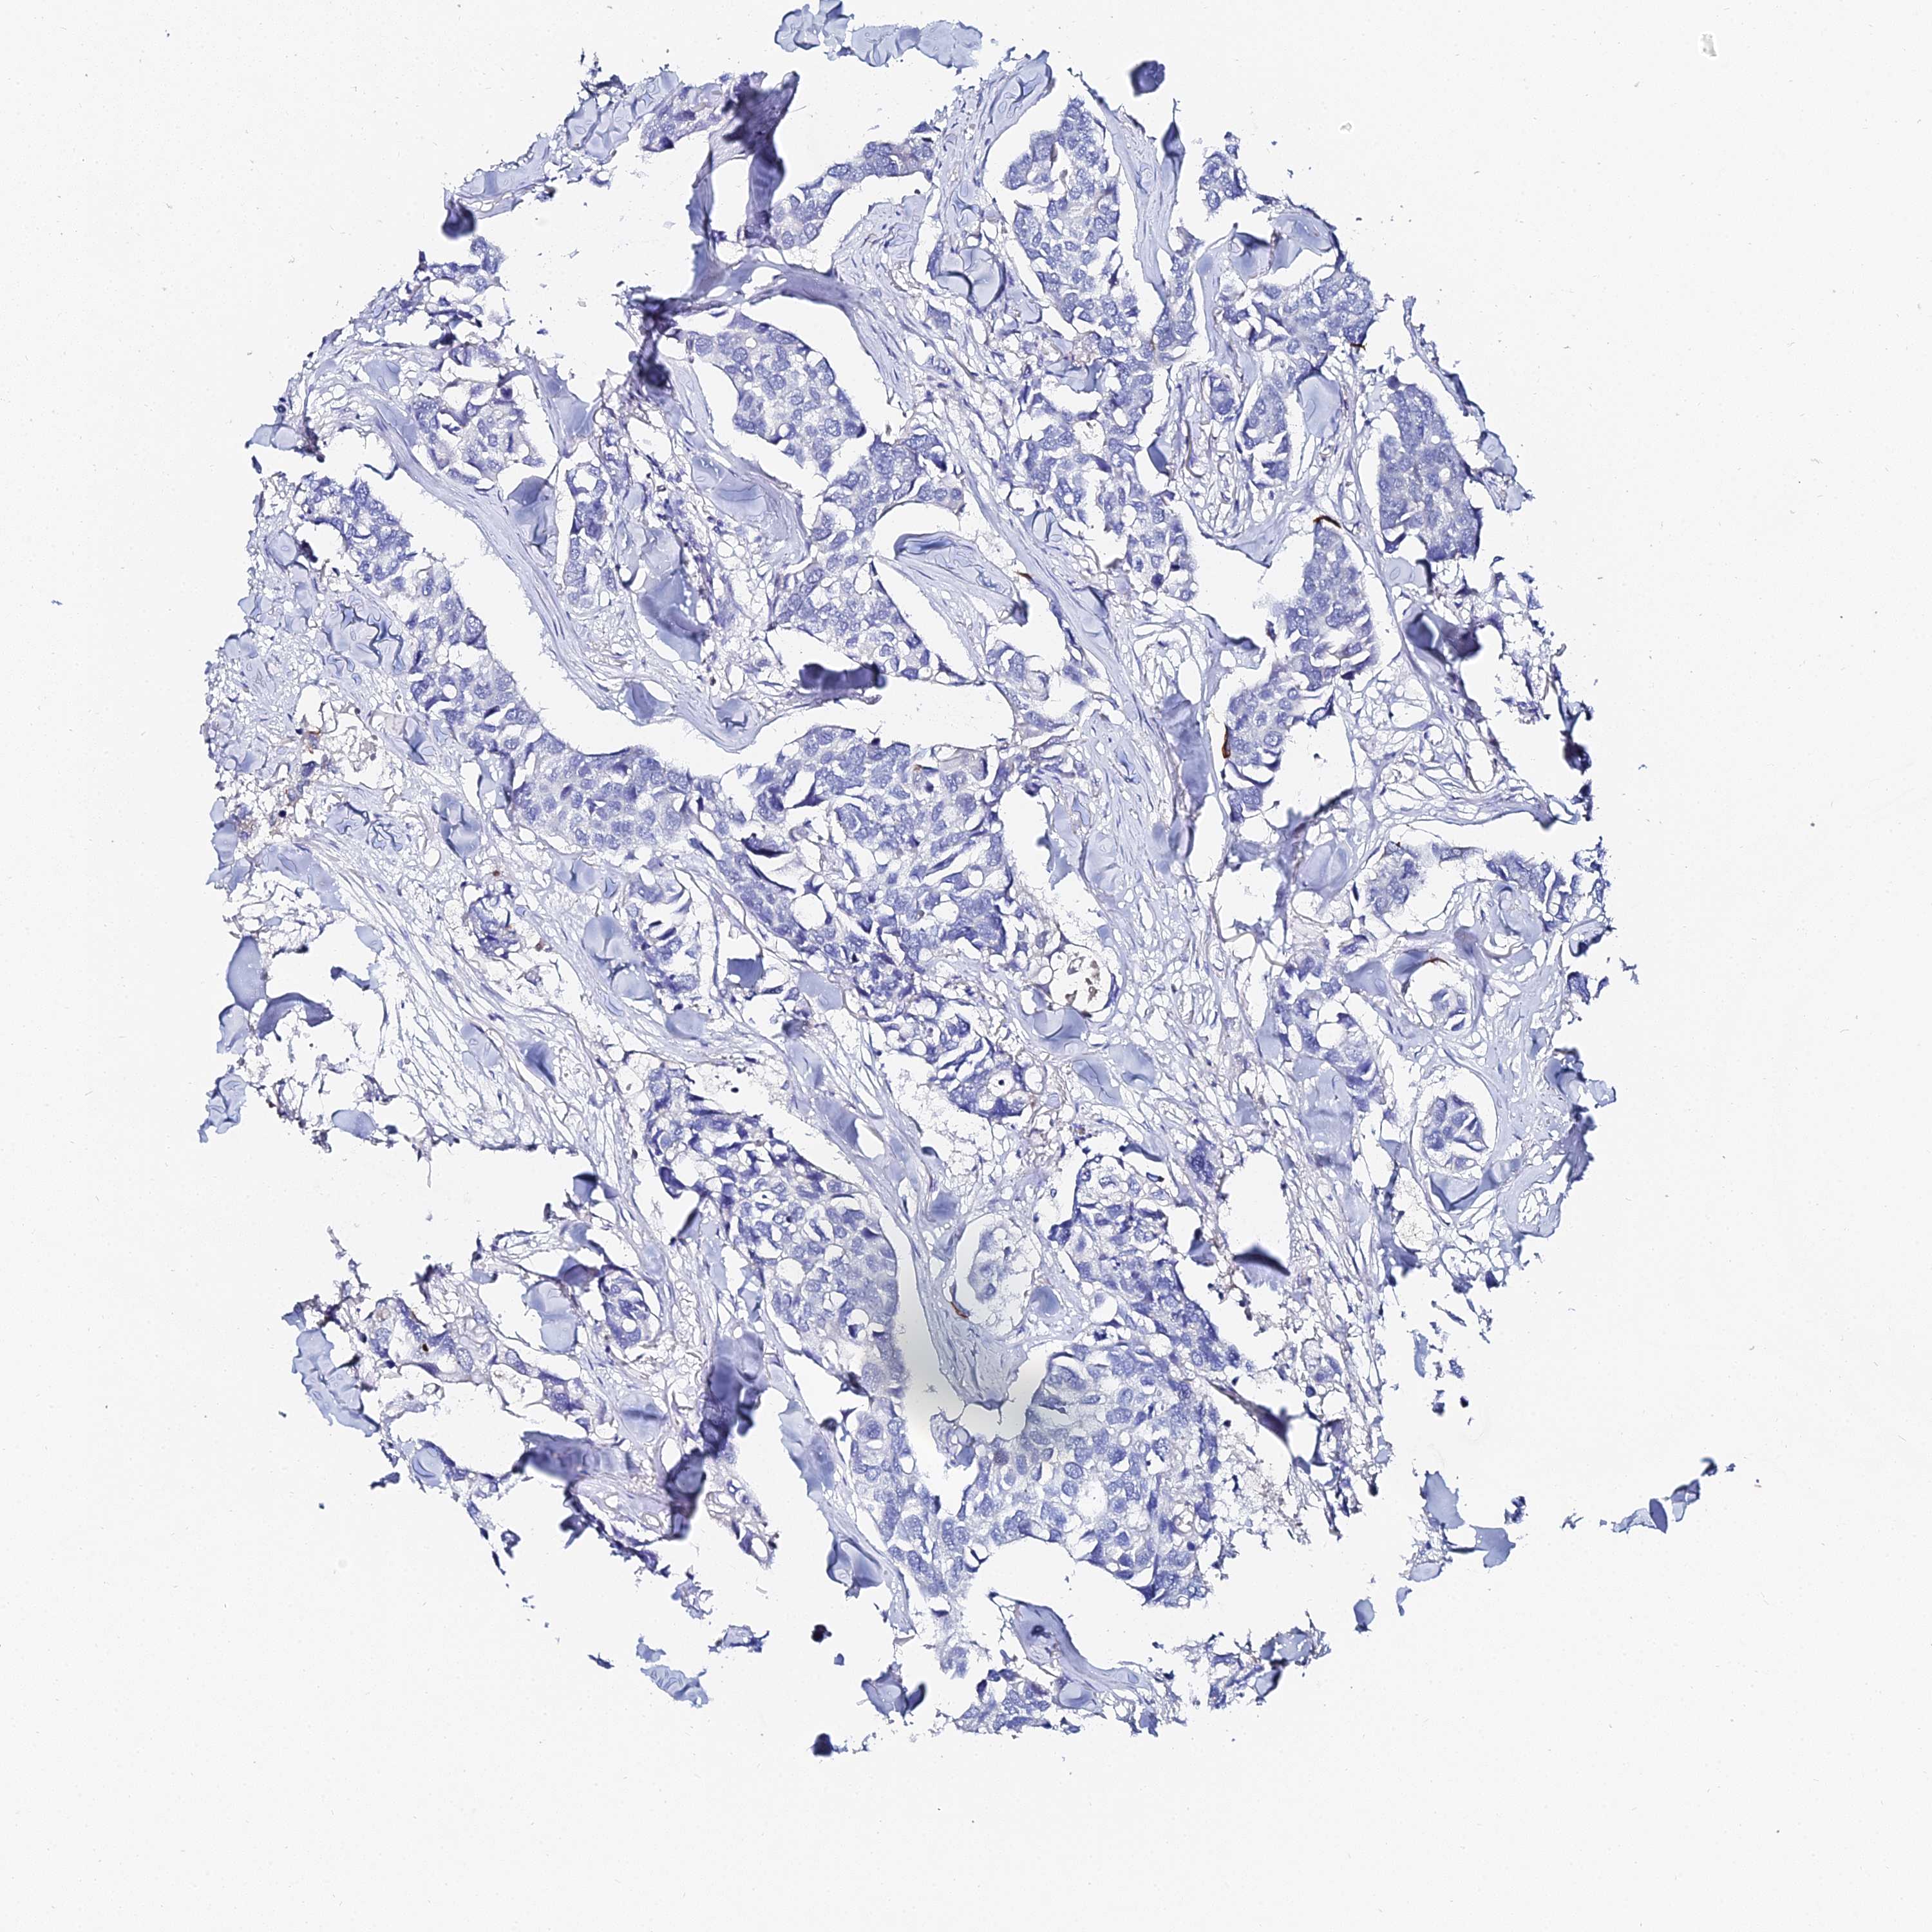

KRT17

CANCER BREAST CANCER Show tissue menu

BRCA TCGA BRCA VALIDATION PROTEIN EXPRESSION

ANTIBODIES

AND

VALIDATION